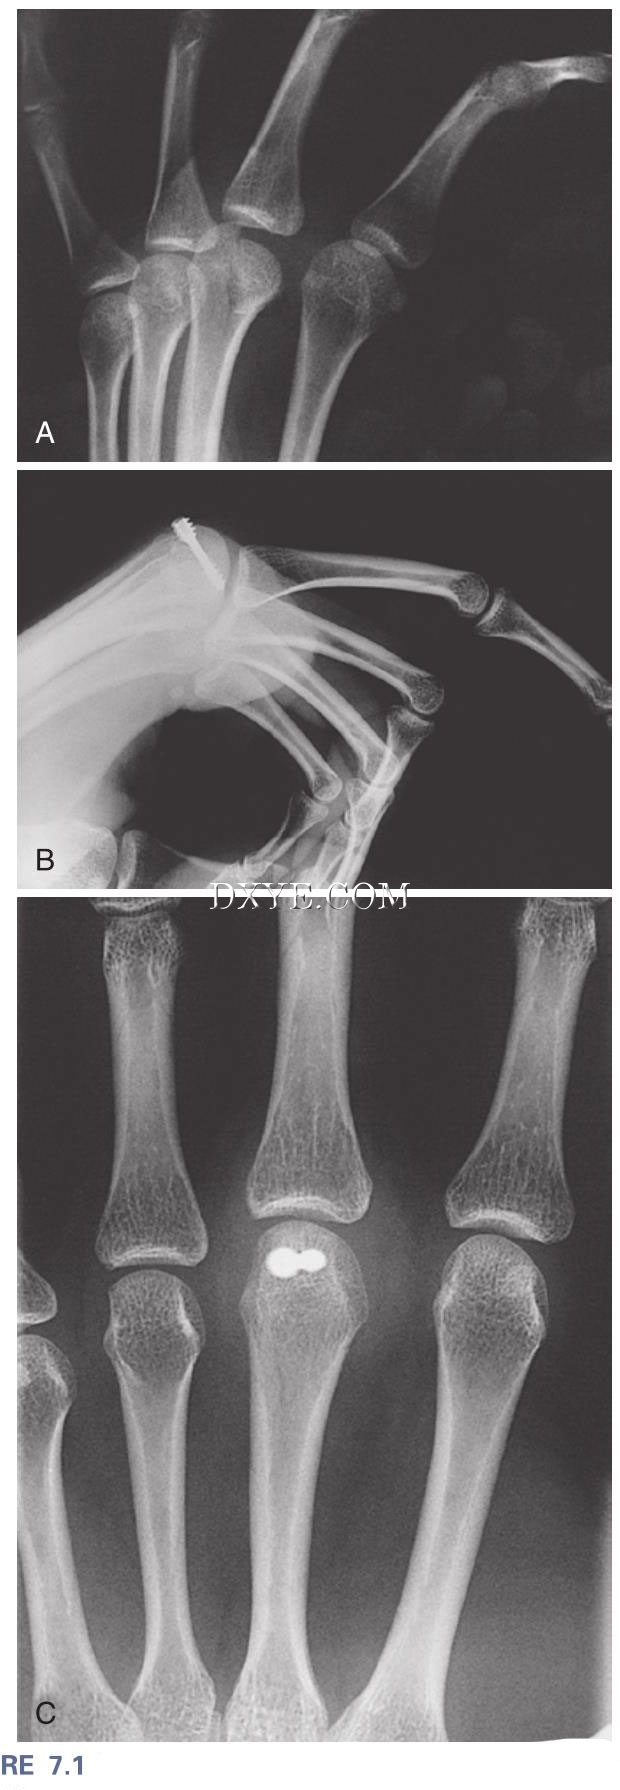

图 7.1  A, 掌骨中指关节矢状骨折。 B 和 C, 术后正位 (B) 和侧 (C) 视图显示解剖复位和无头螺钉固定。 充分的MP流动性被恢复了。